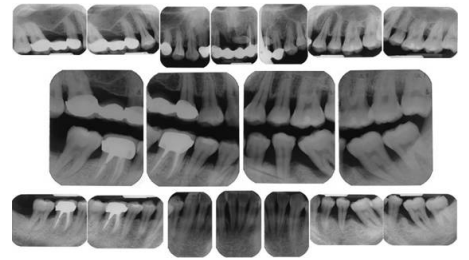

66.一位自述有牙周病的病人前來求診,病人的主訴包括:牙齒疼痛、牙齦腫大、牙齒搖晃嚴重(如下 圖所示),下列何種檢查和處置您認為不適當?

(A) 先瞭解病人的主訴,並在牙周治療前,蒐集所必須的資料,包括口內外檢查、病史詢問、X光片 或是模型的收集 (B)病人的右上側門牙的近心面依1964 Silness & Löe學者牙菌斑指數(plaque index)應紀錄為1 (C)為了降低病人因發炎造成的腫、痛,除了給予物理性潔牙外,亦可合併使用化學性沖洗 (D)病人牙齒搖晃嚴重,除了觀測牙齒的發炎破壞程度,亦需檢查病人是否有咬合震顫(fremitus) 的狀況

67.右下後牙區牙周探測檢查表如下圖所示(GR:gingival recession,PD:probing depth,數字下畫線代表 探測流血),而#46與#47的舌側牙根分岔處均是第一級侵犯,下列敘述有那些是正確?①#47的附連喪失 比#46的嚴重故其整體預後較差 ②因#47牙根分岔較窄(<0.85mm)故其預後比#46較佳 ③#45和#46 的附連喪失相當,但是#45是單根牙故其預後較#46佳

(A)只有①② (B)只有①③ (C)只有②③ (D)①②③